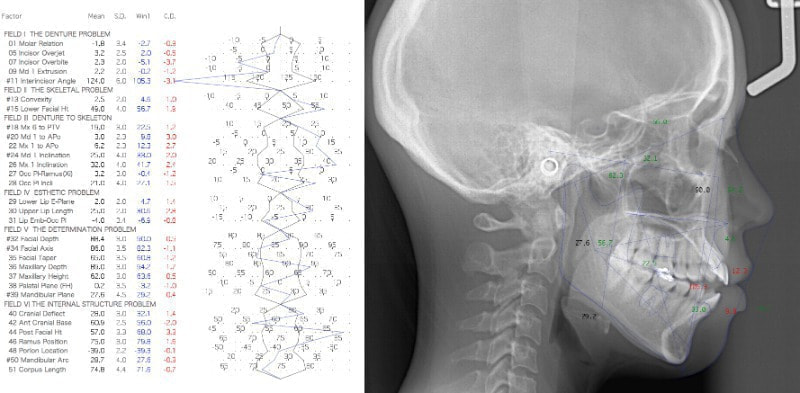

検査時セファロ分析

かなり重度のオープンバイト症例です。骨格的な要素も強く出ております。通常であれば外科矯正適応のパターンですが、当院では矯正治療のみで、外科は行いません。